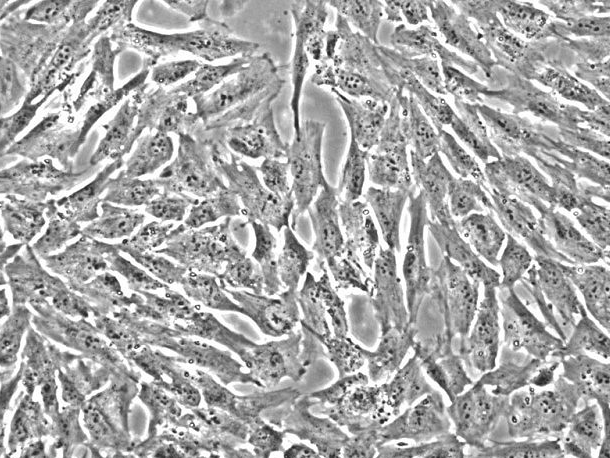

产品名称:HISMC;人肠平滑肌细胞(原代细胞)

来自ScienCell研究实验室的HISMC与人体肠道分离。HISMC在*代冷冻保存并冷冻。每个小瓶含有>5×10^5个细胞,1ml体积。HISMC的特征在于免疫荧光,具有对α-平滑肌肌动蛋白和结蛋白特异的抗体。HISMC对HIV-1,HBV,HCV,支原体,细菌,酵母和真菌均为阴性。在ScienCell研究实验室提供的条件下,HISMC保证进一步扩大15次人口倍增。

平滑肌收缩是胃肠运动的基本事件。尽管尚未定义激发 - 收缩偶联的许多生化机制,但已知细胞溶质Ca 2+是偶联现象中的必要组分。人体肠道的炎症导致平滑肌特异性肌动蛋白水平增加,这反过来促进平滑肌层的增厚。增加的平滑肌肌动蛋白可能影响力的产生,并进一步证明发炎肠道中平滑肌细胞的可塑性[1]。研究还表明,人体肠道平滑肌细胞(HISMC)通过释放IL-6对IL-1β和TNF-α刺激有反应,这可能显着促进整体全身炎症反应[2]。